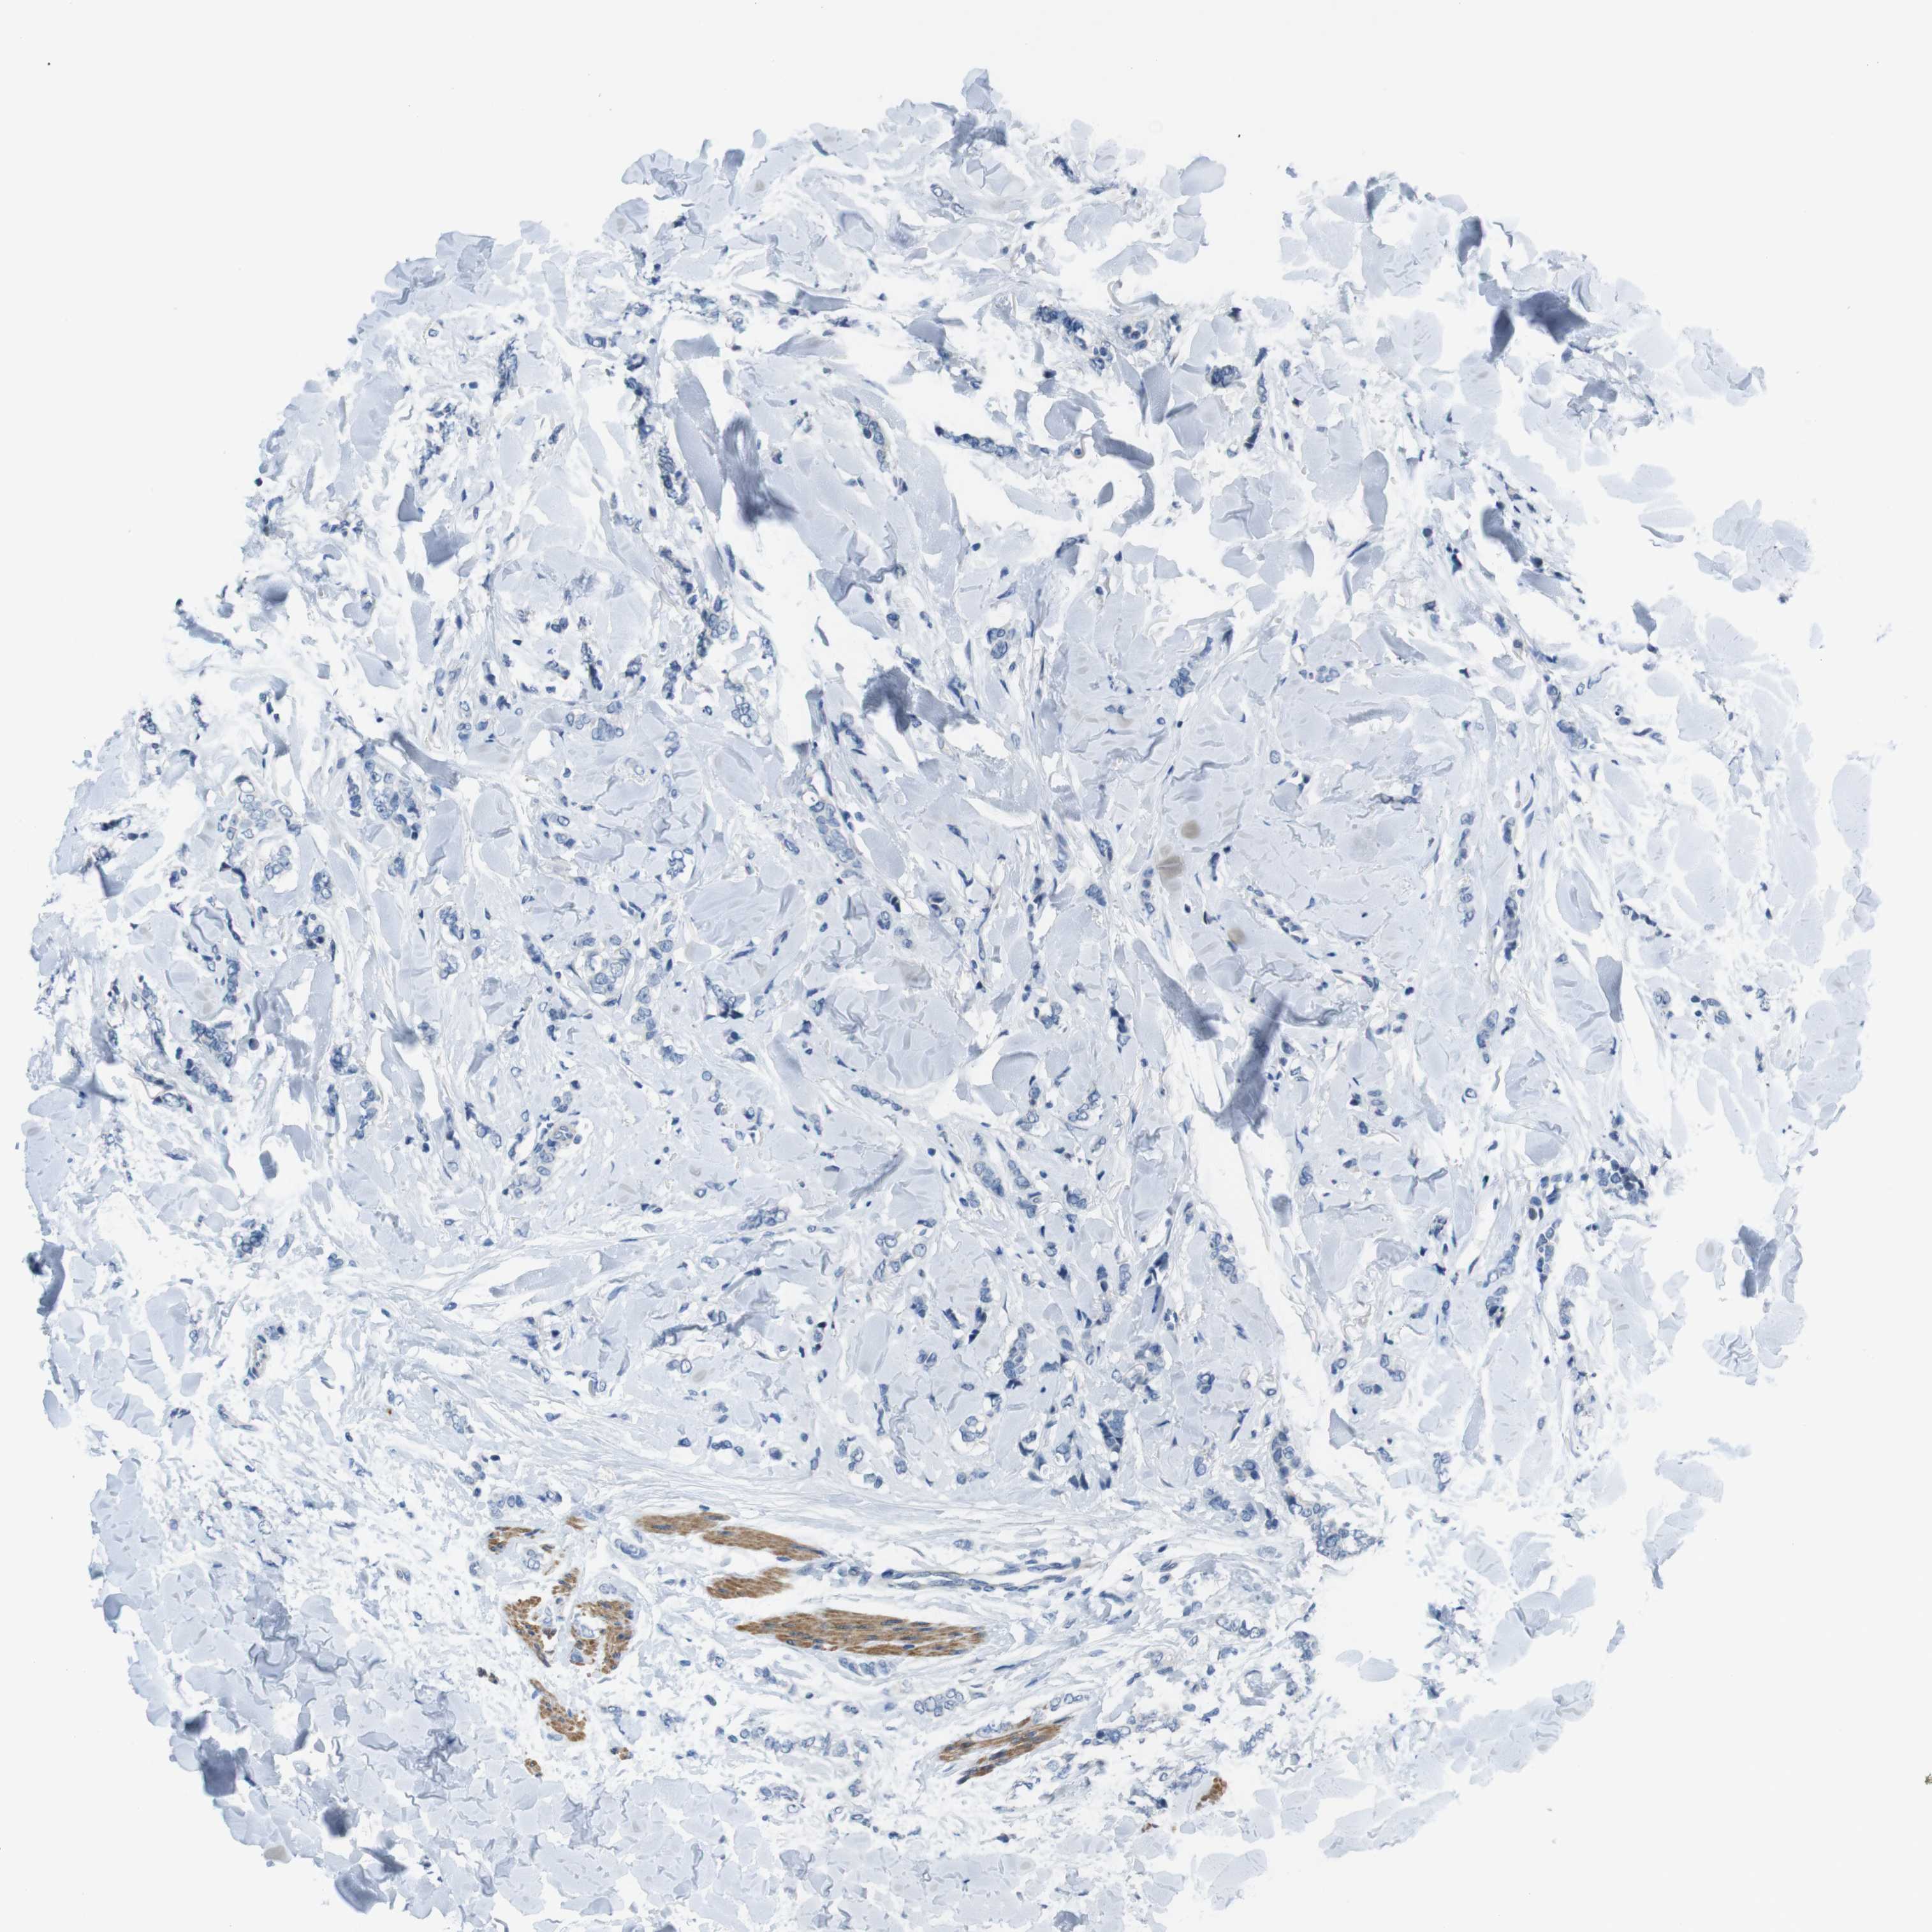

BRCA TCGA BRCA VALIDATION PROTEIN EXPRESSION

ANTIBODIES

AND

VALIDATION